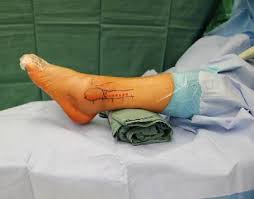

Da dieser Bruch leicht verschoben war musste operiert werden.

Die Schleimhaut die das Sprunggelenk auskleidet entzündet sich und verursacht auch in Ruhe Sprunggelenkschmerzen. Häufig ist bei diesem Knöchelbruch am Wadenbein die Syndesmose verletzt und die Stabilität der Sprunggelenksgabel nicht mehr gewährleistet. Da dieser Bruch leicht verschoben war musste operiert werden. Wenn es sich um eine offene Fraktur handelt durchstößt ein oder mehrere Knochenfragmente die Haut und ist sichtbar. Schwellung nach OP Weber-B-Fraktur oberes Sprunggelenk wie lange. Eine Studie aus Finnland hint. Mein Bein ist noch ziemlich geschwollen und ich fange erst in ein paar Tagen mit Lymphdrainage und Physiotherapie an. Es können außerdem allgemeine Symptome wie Übelkeitund Erbrechen bei einem solchen Bruch auftreten. Die Ärztin hat mir auch eine Bandage verordnet aber ich weiss nicht ob das meine Schwellung nicht nur auf.